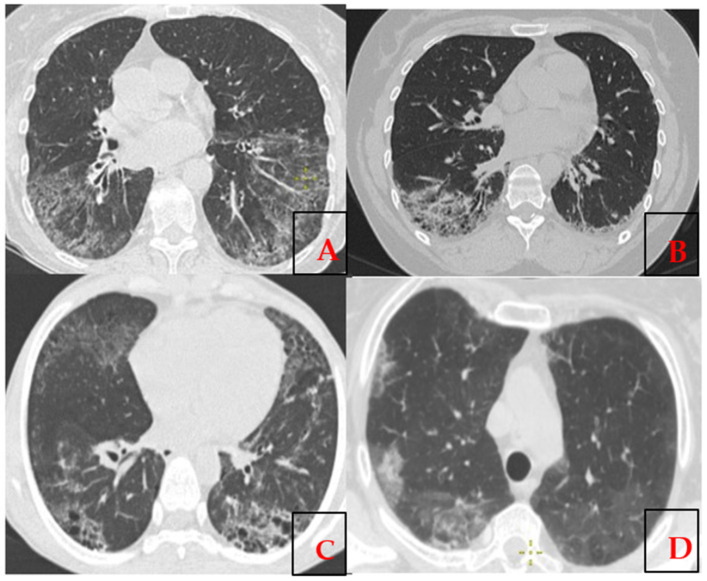

系统性硬化症(SSc)是一种以血管异常、免疫功能障碍和进行性纤维化为特征的自身免疫性结缔组织疾病。SSc最常见的表现之一是间质性肺疾病(ILD),其病程呈进行性,可导致显著的发病率和死亡率。目的:通过对哈萨克斯坦SSc-ILD患者队列的系统回顾和分析,研究SSc-ILD的自身抗体、细胞因子和遗传标记。方法:通过PubMed检索过去10年的“SSc-ILD”、“自身抗体”、“细胞因子”和“基因”。对30例SSc患者的肺受累情况、EScSG评分和改良罗德曼皮肤评分进行评估。ELISA法检测白细胞介素-6,间接免疫荧光法检测HEp-2细胞抗核因子,免疫印迹法检测特异性自身抗体。在离子质子平台上使用120个基因的AmpliSeq面板进行遗传分析。结果:文献综述确定了361篇文章,26篇涉及自身抗体,20个遗传变异和12个细胞因子谱。IL-6、TGF-β、IL-33和TNF-α水平升高与SSc有关。基于系统评价的结果,我们创建了一个针对SSc- ild的初步免疫原性小组,并对哈萨克斯坦SSc患者(n = 30)进行了以下分析。其中14人(46.7%)表现出ILD和/或肺高血压的迹象,经常检测到抗体,如Scl-70、U1-snRNP、SS-A,以及SAMD9L、REL、IRAK1、LY96、IL6R、ITGA2B、AIRE、TREX1和CD40基因的遗传变异。结论:目前的研究证实,在哈萨克斯坦SSc-ILD患者队列中,IRAK1、TNFAIP3、SAMD9L、REL、IRAK1、LY96、IL6R、ITGA2B、AIRE、TREX1、CD40基因存在广泛的自身抗体和变异。

Systemic sclerosis (SSc) is an autoimmune connective tissue disorder characterized by vascular abnormalities, immune dysfunction, and progressive fibrosis. One of the most common manifestations of SSc is interstitial lung disease (ILD), known by a progressive course leading to significant morbidity and mortality. Aim: to investigate autoantibodies, cytokines, and genetic markers in SSc-ILD through a systematic review and analysis of a Kazakh cohort of SSc-ILD patients. Methods: A PubMed search over the past 10 years was performed with "SSc-ILD", "autoantibodies", "cytokines", and "genes". Thirty patients with SSc were assessed for lung involvement, EScSG score, and modified Rodnan skin score. IL-6 was measured by ELISA, antinuclear factor on HEp-2 cells by indirect immunofluorescence, and specific autoantibodies by immunoblotting. Genetic analysis was performed using a 120-gene AmpliSeq panel on the Ion Proton platform. Results: The literature review identified 361 articles, 26 addressed autoantibodies, 20 genetic variants, and 12 cytokine profiles. Elevated levels of IL-6, TGF-β, IL-33, and TNF-α were linked to SSc. Based on the results of the systemic review, we created a preliminary immunogenic panel for SSc-ILD with following analysis in Kazakh patients with SSc (n = 30). Fourteen of them (46.7%) demonstrated signs of ILD and/or lung hypertension, with frequent detection of antibodies such as Scl-70, U1-snRNP, SS-A, and genetic variants in SAMD9L, REL, IRAK1, LY96, IL6R, ITGA2B, AIRE, TREX1, and CD40 genes. Conclusions: Current research confirmed the presence of the broad range of autoantibodies and variations in IRAK1, TNFAIP3, SAMD9L, REL, IRAK1, LY96, IL6R, ITGA2B, AIRE, TREX1, CD40 genes in of Kazakhstani cohort of SSc-ILD patients.